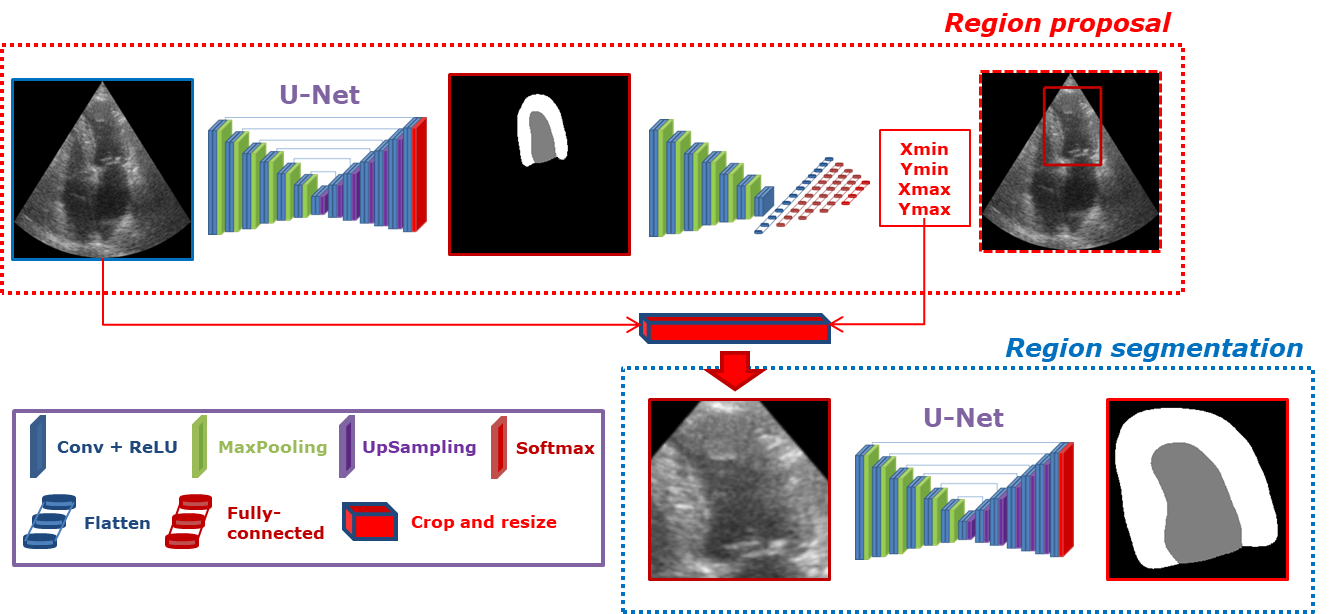

Based on the motivations and the literature review on attention learning presented in the previous sections, we developed a multi-task network to improve the robustness of segmentation in 2D echocardiography. Since the U-Net model already produces high-performance segmentation results in echocardiography [4], we decided to use this architecture as back-bone for our multi-task network, referred to as Localization U-Net (LU-Net) in the sequel. LU-Net aims at locating and segmenting the endocardial and the epicardial borders of the left ventricle through an end-to-end learning procedure. The underlying assumption of this strategy is that the joint optimization of these two tasks should lead to better segmentation results. An illustration of the LU-Net’s overall architecture is provided in Fig. 1. In particular, LU-Net is composed of two networks: one region proposal network for localization and one U-Net for segmentation.

III-B1 Localization part

The region proposal network performs a mapping between the input ultrasound image and four coordinates to define a bounding box (BB) around the structure of interest, namely the union of the left ventricle and myocardium. The reference BB is defined as the minimal bounding box in contact with the epicardium border. The target coordinates are computed with an additional margin as:

where are the coordinates of the reference BB and its width and height. The motivation for adding a margin was to provide some context around the targeted structures for the segmentation task.

III-B2 Segmentation part

The output of the region proposal network is used as an attention mechanism to crop and resize the input ultrasound image. The resulting image is fed to a segmentation network which corresponds to a U-Net(the U-Net1 model described in [4]), currently the most efficient model evaluated on the CAMUS dataset considering a trade-off between accuracy, speed and size.

III-B3 End-to-end approach

In order to make the full network trainable end-to-end, the crop and resize step was implemented using a bilinear differentiable sampling. In addition, the segmentation loss involved in the second U-Net was modified to evolve dynamically over the training phase with respect to the varying ROI. The two U-Nets are independent networks with distinct parameters. At inference time, based on the localization outputs, the final segmentation result is then returned to the original coordinate system of the input image.

Based on this experiment, it is clear that the U-L2-mu model produced the best localization results. We therefore decided to use this network as the region proposal part of the LU-Net architecture, as illustrated in Fig. 1.